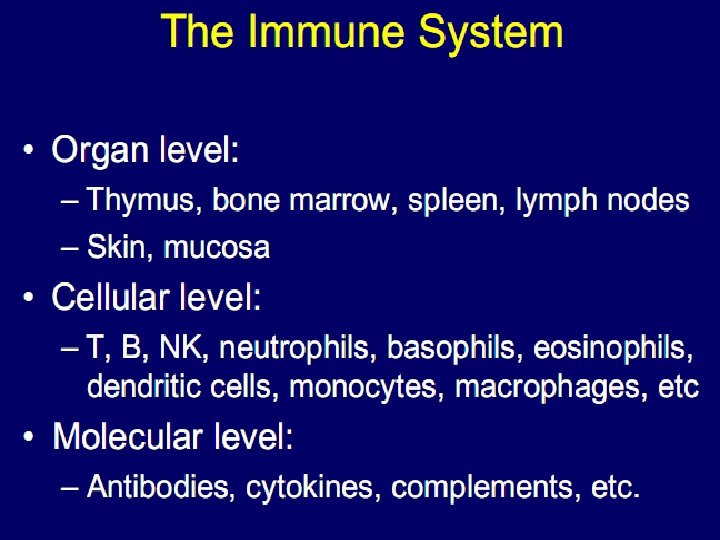

An Immune system is a collection of biological processes within an organism that protects against disease by identifying and killing pathogens and tumour cells. It detects a wide variety of agents, from viruses to parasitic worms, and needs to distinguish them from the organism's own healthy cells and tissues in order to function properly. Antigen is substance that stimulates the production of an antibody when introduced into the organism. Antigens include toxins, bacteria, viruses, and other foreign substances. Antibodies (also known as immunoglobulins, abbreviated Ig) are gamma globulin proteins that are found in blood or other bodily fluids and are used by the immune system to identify and neutralize foreign objects, such as bacteria and viruses.

The major components of the immune system are: • Immunocompetent cells • Antibodies • Complement system • Bone marrow • Thymus • Spleen • Lymph nodes • Tonsils

Immunocompetent cells: 1. T-lymphocytes {T-helper, T-suppressor, T-cytotoxic (killer cells), T-memory cells} 2. Natural killer cells(NK-cells) 3. B-lymphocytes 4. Plasma cells 5. Macrophages 6. Granulocytes of the blood(Neutrophilic, Eosinophilic, Basophilic Leucocytes) 7. Monocytes 8. Mesenhymal reticular cells 9. Epithelial reticular cells 10. Antigen Presenting Cells (APC) {Dendritic cells, Langerhans’ cells of the skin, Kupffer’s cells of the Liver, Dust cells of the Lung etc. )